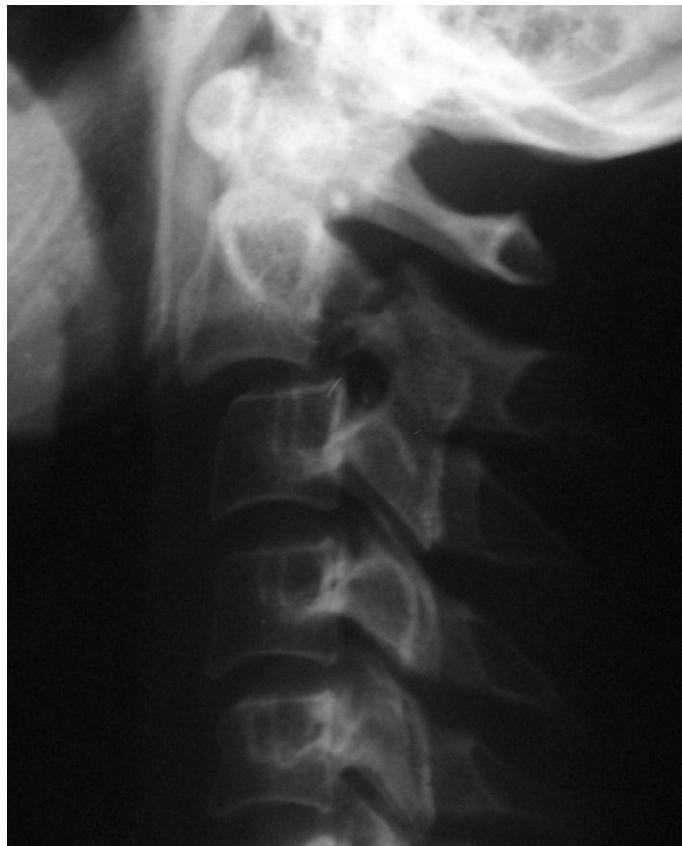

C-Spine X-ray

- Views:

- Lateral View: Must show C1 down to the C7-T1 junction.

- AP View.

- Odontoid (Open Mouth) View: Used to visualize C1 and C2 (especially the dens).

- Pathology:

- Odontoid Fracture (C2): Seen on the open mouth view.

- C2 Fracture (Hangmanโs fracture) can be seen on the lateral view.